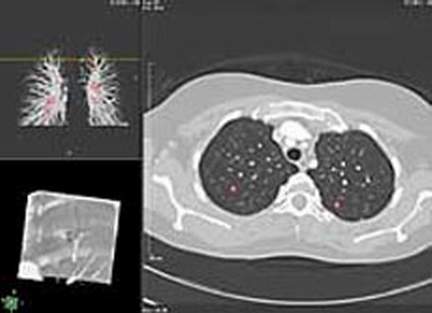

计算机能比医生更快查明早期肺癌(图)

美国X光医生很快就能在计算机分析系统的帮助下查明早期肺癌。美国食品与药品管理局(FDA)已批准由加利福尼亚R2技术公司研制的ImageChecker CT-LN 1000系统进行试验。

分析图像工艺能使该系统仔细观察计算机X射线层析拍摄肺部微小生成物的结果,这样小的生成物很容易被X光医生忽略。其中不少节结是良性的,但它们有可能会发展成肺癌。

R2技术公司的专家指出,计算机可以成为X光医生的第二双眼睛,能使他们更仔细地检查X光照片。该公司已向美国食品与药品管理局提出系统有效的证据,参与这项研究结果的共有15名X光医生,现已查明,ImageChecker CT-LN 1000系统能发现肺部更多小节结。

检查早期肺癌是一项特别重要的任务,在美国14%的肺癌患者只能存活5年,但是如果能在肺癌早期阶段确诊,则可以使存活5年的患者人数增加到42%。仅在美国每年约有157000人因肺癌而死亡。